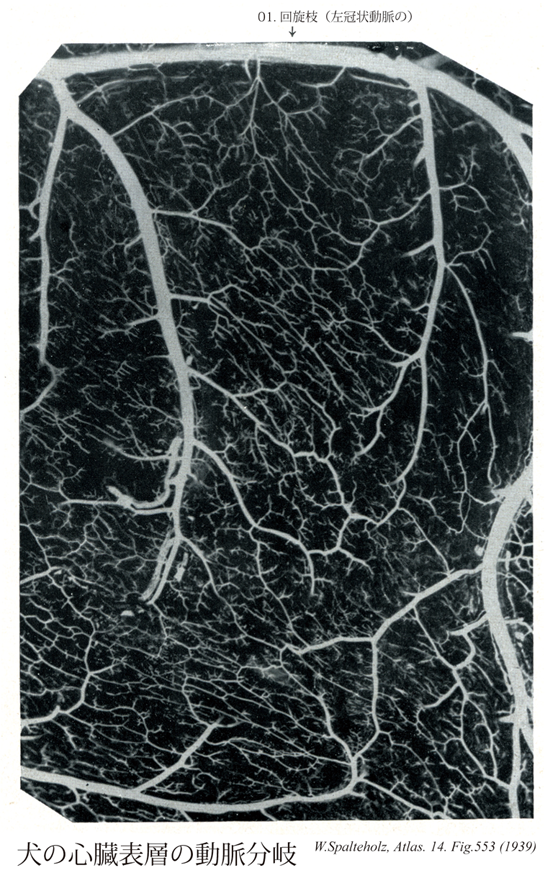

553

- 01【Circumflex branch of left coronary artery回旋枝(左冠状動脈の) Ramus circumflexus (Arteria coronaria sinistra)】 Continuation of the left coronary artery that travels in the left coronary sulcus.

→(左冠状動脈の回旋枝は前室間枝とともに左冠状動脈の延長で左冠状溝を走る枝。冠状動脈内を左方、ついで下方にすすみ心房、心室に分布する。)